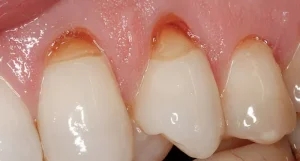

Gingivitis, a common and mild form of gum disease (periodontal disease), causes irritation, redness, and swelling (inflammation) of your gingiva, the part of your gums